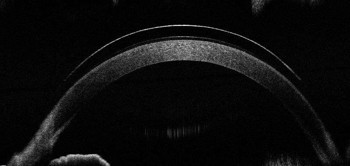

After a discussion with the patient, the decision was made to proceed with scleral lens fitting. I prefer to use the sMap3D device for scleral lens fitting as it allows for a fully customisable lens design over 360° (Figs 2 and 3)8. After fitting and dispensing the sMap3D scleral lenses, the patient was asked to start wearing his lenses while using his computer at work.

Fig 3. OCT scan of the lens on the eye